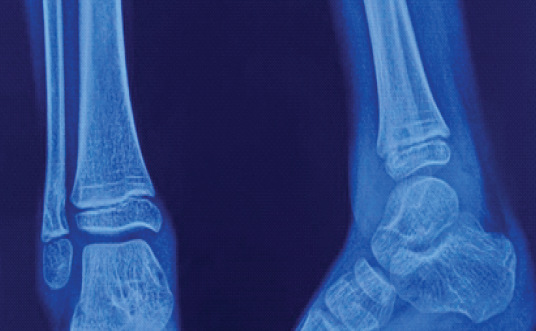

Plain radiographs of the ankle show a lytic lesion in the distal fibula just proximal to the physis (Fig. 2).

Figure 2: Plain radiograph of the ankle joint showing a lytic lesion at the anteromedial cortex of the distal fibula just proximal to the physis.